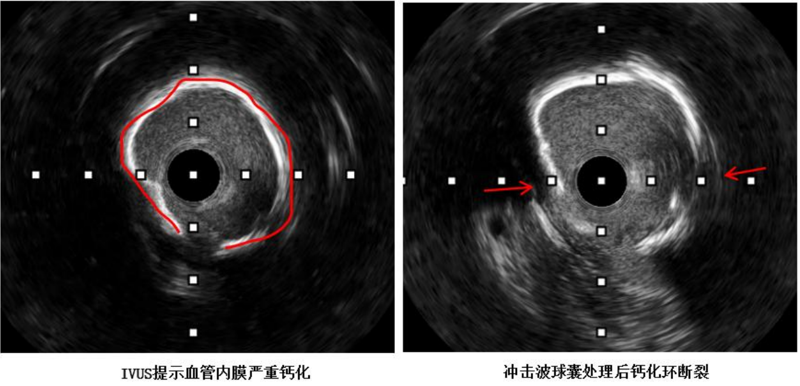

近日,中山大学附属第一医院(简称中山一院)广西医院心血管内科冠脉介入手术团队运用DEEPQUAKE-C冠脉血管内冲击波系统,顺利为一名冠脉严重钙化病变的冠心病患者开通堵塞的血管并完成支架植入,完成了DEEPQUAKE-C上市后全国首批、广西首例临床应用。68岁的杨阿姨(化名)近两年来反复出现胸痛症状,严重影响正常生活,得知我院来了很多中山一院的派驻专家,为寻求进一步治疗,她来到我院心血管内科住...